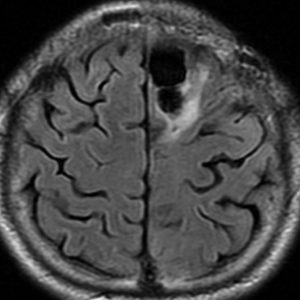

退形成性星細胞腫 グレード3の膠芽腫としての再発例

左上前頭回のびまん性グリオーマ diffuse glioma です。手術でほぼ全摘 gross total removalして54グレイの放射線治療とテモゾロマイド化学療法をしました。病理診断は,oilg 2陽性,1p/19q染色体の欠失はない退形成性乏突起星細胞腫 グレード3とされました。全体的にはグレード2であるとの病理医の意見もありましたし,当時は北大病院でもIDHの正確な分子病理診断は行われていませんでした。

5年後です。上前頭回の病巣は落ち着いていましたが,初回にはなかったはずの場所,脳梁前方に急激な再発増大を生じました。また手術で全摘出 gross total removalして,かなり絞った領域に60グレイの放射線治療とテモゾロマイド,アバスチンの投与をしました。病理診断は,IDH wild-tpye, 1p/19q non-codel, MIB 40%, ATRX positive, MGMT negativeの膠芽腫でした。

その後またしばらく寛解継続できました。